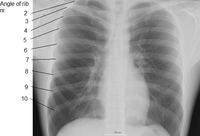

Thoracic cage with spine

Human ribs (shown in red). It consists of 24 ribs. Left and right of first rib to twelfth rib.